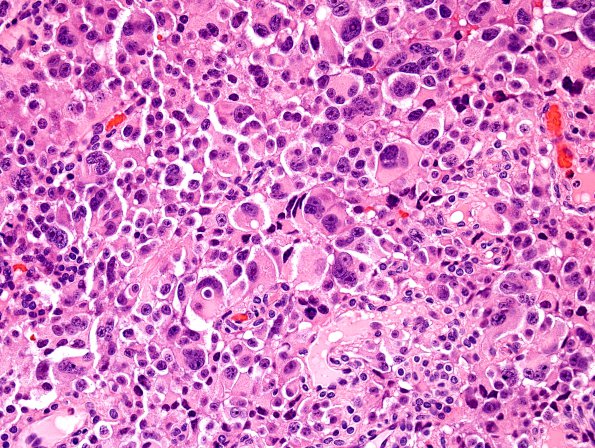

Washington University Experience | NEOPLASMS (METASTASES) | Microscopic | 3A2 Pituitary Carcinoma, metastatic (Case 3) H&E 2.jpg

The permanent specimen on this case continues to show marked atypia with numerous bizarre giant cells. (H&E)